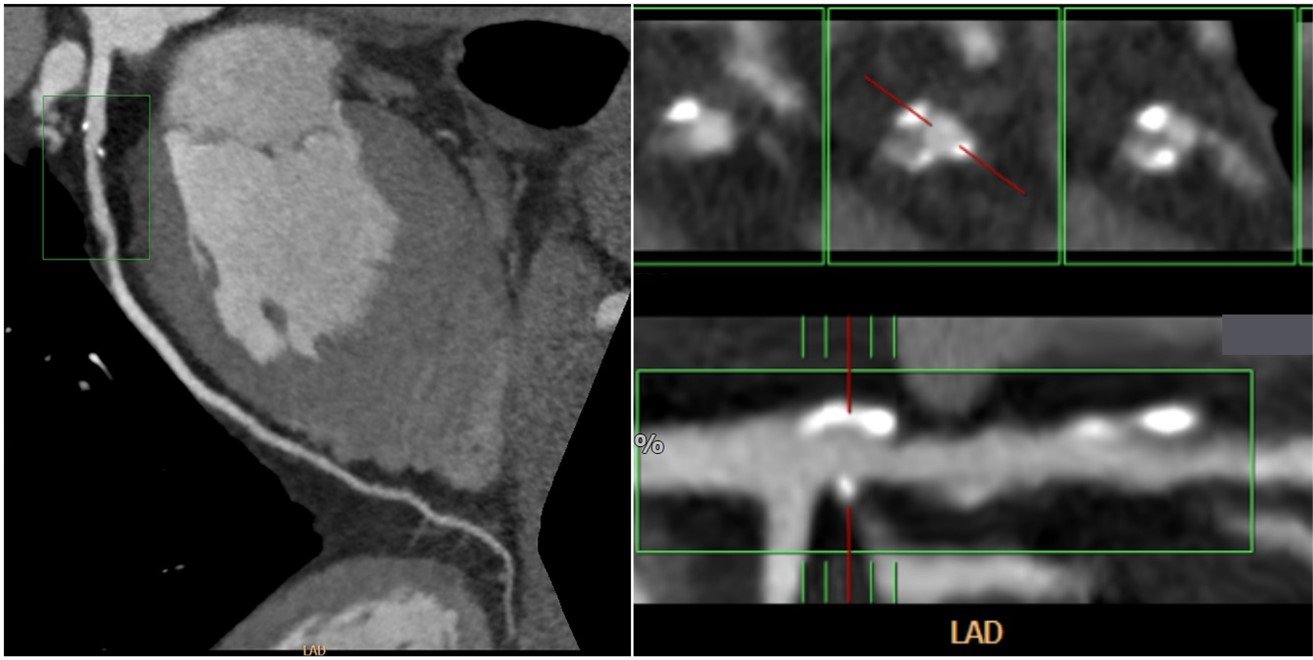

ST-elevation myocardial infarction (STEMI) patients should be managed with fibrinolytic administration or primary percutaneous coronary intervention (PCI) [6]. As mentioned earlier, due to the limited cardiac interventionist/cardiothoracic surgeon in developing countries’ hospitals, administering fibrinolytic is the first attempt that can be made in all hospitals. However, if the use of fibrinolytic is contraindicated, a right referral should be made. The use of CCTA in the situation will be helpful in identifying patients with: a) left main LAD with intermediate-high synergy between percutaneous coronary intervention with TAXUS and cardiac surgery (SYNTAX) score; b) three-vessel CAD without diabetes with intermediate-high SYNTAX score; c) and three-vessel CAD with diabetes with low-high SYNTAX score who are more recommended to undergo coronary artery bypass grafting (CABG) than PCI [54]. When diagnosed with CCTA, the patient can be referred to the hospital by a cardiothoracic surgeon, and the patient can be planned to undergo CABG directly. On the other hand, patients with other coronary obstruction that is not included in the indication for CABG should be referred to an interventionist for PCI. The management algorithm for patients planning to undergo cardiac intervention can be seen in Figure 1.

CCTA: coronary CT angiography, LAD: left anterior descending.